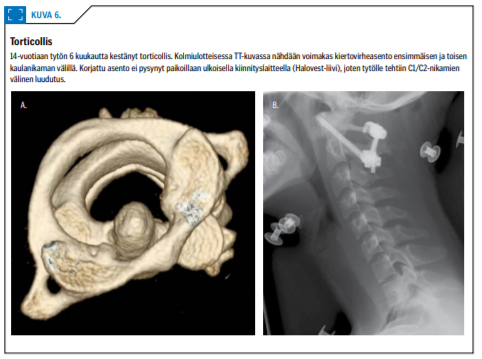

Torticolliksen taustalla on usein ylähengitysteiden infektio (Grieselin oireyhtymä) tai vähäinen tapaturma (10). Kliininen kuva on tyypillinen: leuka osoittaa keskilinjasta sivuun ja pää kallistuu vastakkaiselle puolelle. Valtaosalla vaiva menee ohi muutamassa päivässä oireenmukaisella hoidolla.

Mikäli oireenmukainen hoito ei auta, lapsi on syytä lähettää erikoissairaanhoitoon, jossa tehdään jatkotutkimuksena kaularangan tietokonekerroskuvaus (kuva 6 «»8). Jos vaivalle ei löydy selitystä, asetetaan lapsi yön ylitse ns. remmivetoon (Glissonin veto). Tämä yleensä laukaisee tilanteen. Jatkohoitona käytetään kovaa yksilöllistä kauluria kahden viikon ajan.

Pitkittyneen torticolliksen hoito on hankalampaa: suljettu paikalleen asetus yleisanestesiassa tai luudutusleikkaus.